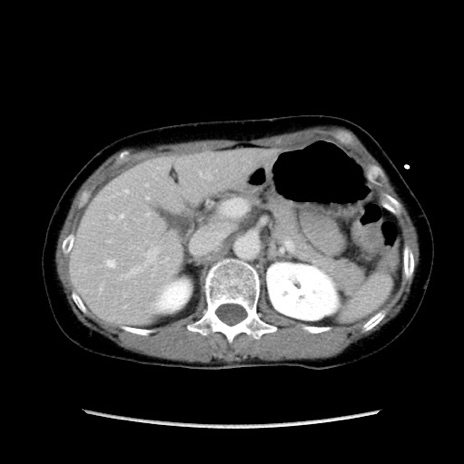

症例32(横断像)

【症例】40歳代 女性

【主訴】上腹部痛、嘔気・嘔吐

【現病歴】約9時間前頃から急に上腹部痛、嘔気、嘔吐が出現。改善しないため救急要請。

【既往歴】子宮頚癌(広汎子宮全摘術、放射線療法)、腸閉塞

【身体所見】腹部:平坦、軟、腸雑音亢進、上腹部を中心に腹部全体に圧痛あり。

【データ】WBC 8400、CRP 0.03